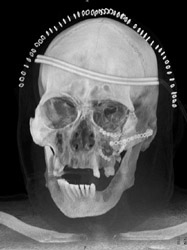

Post Repair of Mandible Fractures